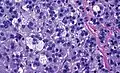

Histopathology

The microscopic histopathology analysis of the tissue samples obtained from the adrenal cortex of individuals presenting with adenoma-associated symptoms such as primary aldestronism (PA) indicates that adenoma cells are relatively larger with different cytoplasm, and increased variation in nuclear size. This indication is based on comparison between the healthy (normal) and affected (adenoma-associated) adrenal cortex tissue samples.

Adrenocortical adenoma with focal high grade nuclear atypia